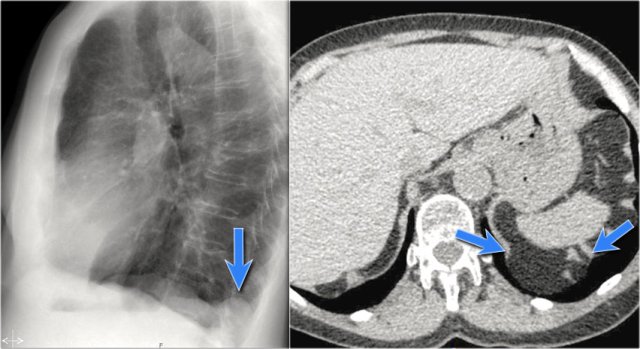

A common incidental finding in adults is a Bochdalek hernia, which is due to a congenital defect in the posterior diaphragm (arrows).

In most cases it only contains retroperitoneal fat and is asymptomatic, but occasionally it may contain abdominal organs.

Large hernias are sometimes seen in neonates and can be complicated by pulmonary hypoplasia.